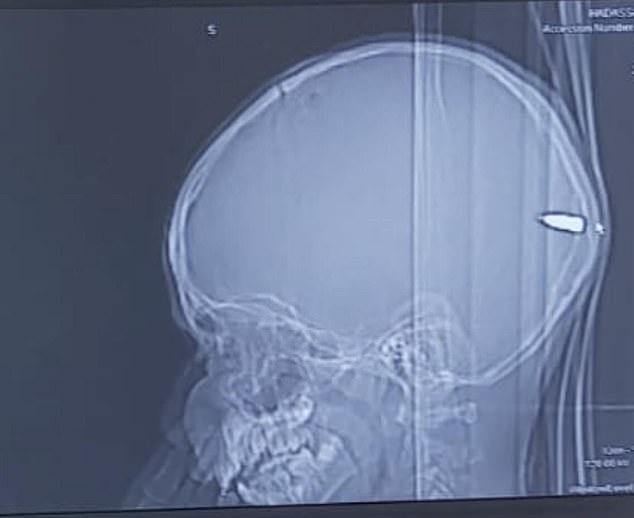

La spital, medicii au observant că băiatul, care a ajuns conștient la ei, avea o mica rană în spatele capului. La o radiografie, s-a văzut că acesta avea un glonț în creier.

Și-au dus copilul la spital, pentru că era tot timpul somnoros! Când medicii le-au arătat o radiografie, au suferit un șoc! Foto

Neurochirurgul care a înlăturat glonțul, într-o operație ce a durat două ore, a spus că părinții copilului habar n-aveau că acesta a fost împușcat și a precizat că băiatul a fost foarte norocos să supraviețuiască.